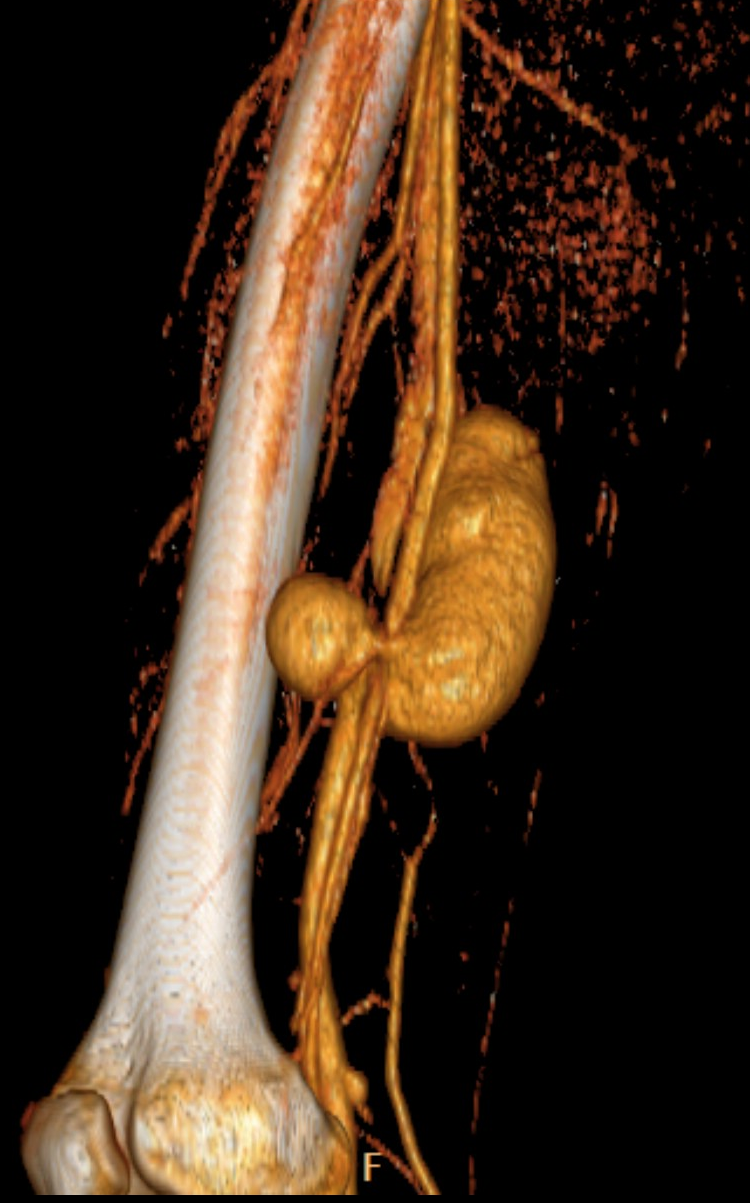

• A knife falling from a kitchen table stuck into the right thigh of an 18 year old young man. Increased femoral circumference and pulsating mass were seen. In the upper image with femoral Duplex sonography pseudoaneurysm of the femoral artery is detected

In the middle with a CT angiography the pseudoaneurysm shows contrast enhancement.

In the lower image 3D reconstruction of the CTA

11. A knife falling from a kitchen table stuck into the right thigh of an 18 year old young man. Increased femoral circumference and pulsating mass are seen. In the upper image with femoral Duplex sonography pseudoaneurysm of the femoral artery is detected In the middle with a CT angiography the pseudoaneurysm shows contrast enhancement. In the lower image 3D reconstruction of the CTA